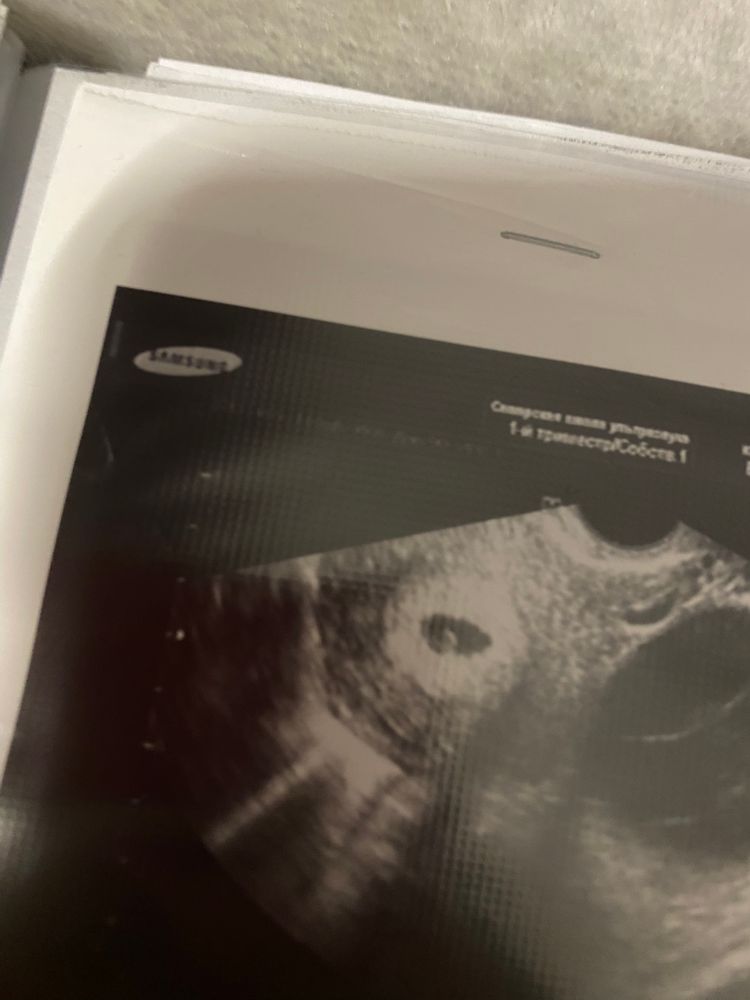

УЗИ 5 недель у подруги, нет эмбриона, переживает. Что делать?

Ходила в 5 и 2. ПЯ 11 мм, желточный мешок. Эмбриона пока не видно. Назначили на 17 мая будет 6 и 6. Жду и надеюсь что эмбрион найдут

У меня так же было , узист говорила что эмбрион очень маленький , только образуется , там была прям совсем маленькая точка , почти как у вас